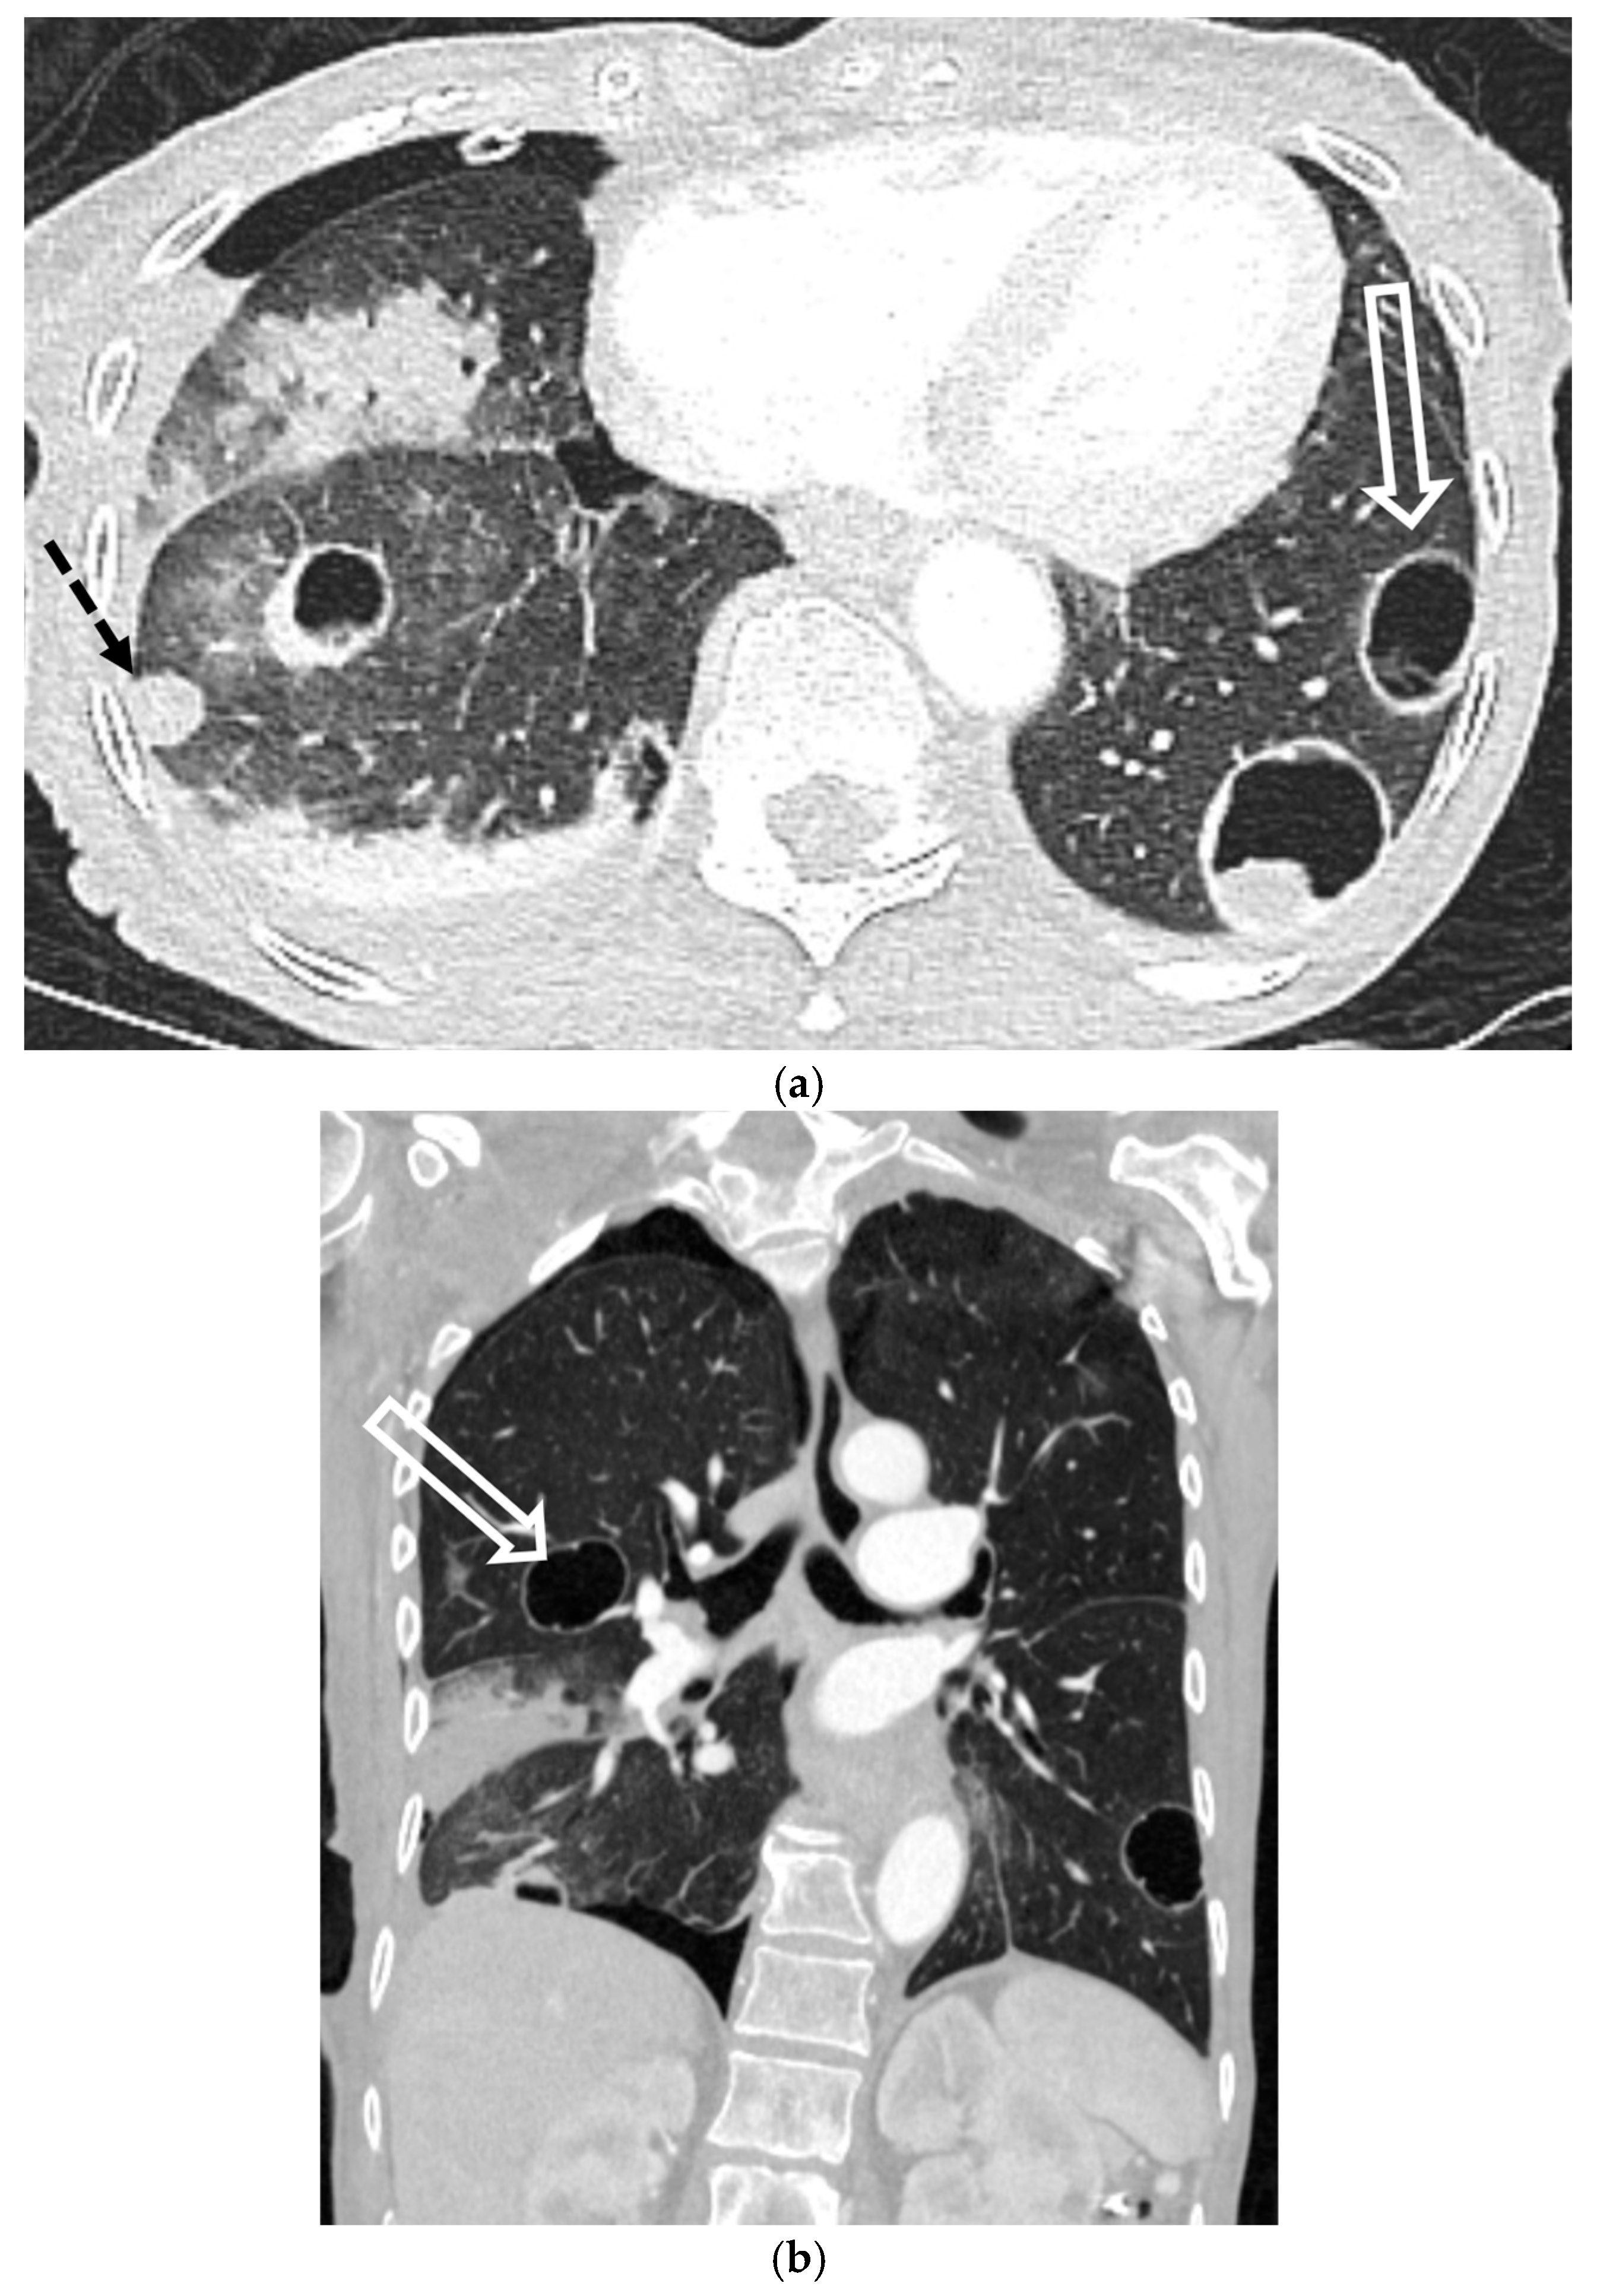

5.5.1. Pulmonary Langerhans Cell Histiocytosis (PLCH)

5.5.2. Lymphangioleiomyomatosis (LAM)

5.5.3. Birt–Hogg–Dubé Syndrome (BHDS)